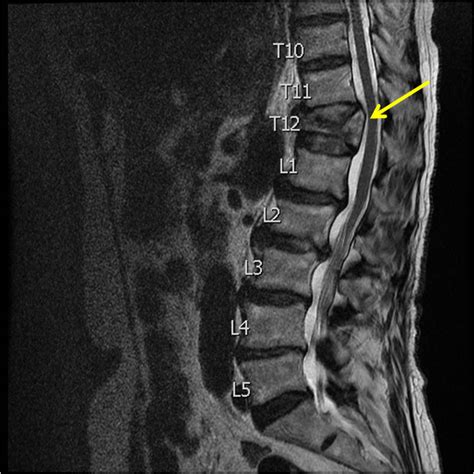

• MRI Scans: MRIs are useful for evaluating soft tissues, such as ligaments and spinal cord. They can help detect nerve compression or other complications.

• Bone Density Tests: Also known as DEXA scans, these tests measure bone density and can help diagnose osteoporosis, a common cause of compression fractures.